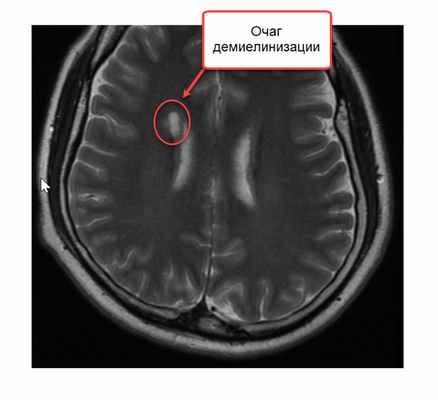

Признаки рассеянного склероза выявляют во время проведения МРТ головного мозга. Делать такое обследование нужно на высокопольном томографическом аппарате мощностью индукции не менее 1,5 Тесла, чтобы шаг сканирования был не более 2 мм. Тогда диагносты не пропустят даже самых мелких очагов возникновения РС. В идеале МРТ головного мозга при подозрении на рассеянных склероз проводят с контрастированием. Инъекция красящего препарата максимально увеличивает контрастность тканей, а по характеру накопления и отдаче контраста врачи могут судить о том, являются ли очаги поражения рассеянным склерозом или другой формой демиелинизирующих заболеваний.

Рассеянный склероз на МРТ без контраста будет виден только своими крупными очагами на поздней стадии, когда есть уже клинические проявления. Также при нативном протоколе сканирования его можно спутать с другими патологическими состояниями. На МРТ снимках очаги, указывающие на демиелинизацию, могут иметь совершенно разный генезис. Например, это может быть:

Как распознают рассеянный синдром на снимках? При рассеянном склерозе на снимках заметно характерно типичное распределение очагов в белом веществе головного мозга. Кроме того, для данного диагноза характерно поражение мозолистого тела, дугообразных волокон, височных долей, мозгового ствола, мозжечка и спинного мозга. Такое распределение очагов нехарактерно для иных патологических процессов, поэтому трудностей при постановке диагноза обычно не возникает. При ангиопатии возможны поражения ствола мозга, однако они обычно симметричны и располагаются центрально, в то время как очаги при рассеянном склерозе локализованы по периферии.

В методе магнитно-резонансной томографии, исходя из названия, применяется иная физическая основа. Кратко опишем этот метод. Итак, из школьного курса физики мы знаем, что существует магнитное поле. Оно есть у всех тел в природе: у нашей Земли, у нашего с Вами тела, у каждого атома нашего тела. Поэтому к каждому телу можно пририсовать стрелку, показывающую направление магнитного поля. Если к атому прилагается внешнее магнитное поле, более сильное, чем у атома, то магнитное поле атома стремится выстроиться вдоль внешнего магнитного поля, параллельно ему. Насколько быстро и насколько точно встанет стрелка магнитного поля атома зависит от свойств самого атома: одни атомы выстраиваются быстро и ровно по направлению внешнего поля, другие с отклонением и медленно. В магнитно-резонансном томографе подается мощнейшее магнитное поле, чаще всего его напряженность составляет 1,5 Тл. К примеру, магнитное поле всей Земли составляет 0,00005 Тл. Магнитно-резонансный томограф представляет собой очень большой магнит, в центре которого напряженность магнитного поля наибольшая. Вас кладут на кушетку, затем кушетка начинает двигаться к центру магнита, похожего на трубу. Когда Вы достигаете центра магнита, то начинается процесс исследования. Магнитные поля всех атомов Вашего тела выстраиваются вдоль поля большого магнита (все маленькие стрелки встают параллельно большой стрелке). Затем перепендикулярно к основному полю магнита подается кратковременный импульс другого сильного поля. Это приводит к наклону всех маленьких стрелок атомов Вашего тела – они выстраиваются уже вдоль этого кратковременного, но очень сильного магнитного поля. Грубо говоря, все магнитные оси атомов ложатся на бок. Когда действие импульса заканчивается, магнитные стрелки атомов вновь возвращаются в положение вдоль направления магнитного поля основного магнита (вдоль трубы). Так вот, скорость возврата магнитных осей из положения на боку в вертикальное положение у разных атомов различно. У атомов водорода оно одно, у атомов кислорода другое, у атомов меди третье, у атомов железа четвертое. А так как каждый участок тела, каждый участок головного мозга состоит из разного количества разных атомов, то и возврат атомов к вертикальному положению осей будет от каждого микроскопического участка головного мозга разным. Существует два основных вида изображений: T1-взвешенное и T2-взвешенное. На Т1-взвешенном изображении фиксируется скорость возврата атомов из положения на боку в вертикальное положение. На Т2-взвешенном изображении время удержания атомов в положении на боку после кратковременного перпендикулярного импульса. Компьютерная программа обрабатывает микроскопические участки мозга по этим параметрам и формирует изображение. Участки демиелинизации существенно отличаются по количеству и спектру атомов от здоровой ткани и видны на Т2-взвешенном изображении в виде белых очагов.

Следует упомянуть и про режим FLAIR: построение изображения в этом режиме происходит путем удаления (не учета) молекул воды, что дает более четкую и более полную картину очагов демиелинизации.